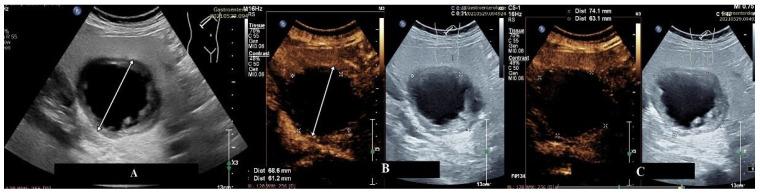

Contrast-enhanced ultrasound (CEUS) has become the preferred method for many clinicians in evaluating focal liver lesions (FLLs) initially identified through standard ultrasound. However, in clinical practice, certain lesions may deviate from the typical enhancement patterns outlined in EFSUMB guidelines. This study aims to assess FLLs that remained inconclusive or misdiagnosed after CEUS evaluation, spanning eight years of single-center experience. Following CEUS, all FLLs underwent secondary imaging (CT, MRI) or histopathological analysis for diagnostic confirmation. From the initial 979 FLLs, 350 lesions (35.7%) were either inconclusive or misdiagnosed by CEUS, with hepatocellular carcinoma (HCC) and liver metastases constituting the majority of these cases. The most frequent enhancement pattern in inconclusive lesions at CEUS was hyper-iso-iso. Factors such as advanced liver fibrosis, adenomas, and cholangiocarcinoma were significantly associated with higher rates of diagnostic inaccuracies. Advanced liver fibrosis, adenomas, and cholangiocarcinoma were significantly associated with increased diagnostic challenges, emphasizing the need for supplementary imaging techniques.

超声造影(CEUS)已成为许多临床医生在评估最初通过标准超声发现的肝脏局灶性病变(FLLs)时的首选方法。然而,在临床实践中,某些病变可能偏离欧洲超声医学与生物学联合会(EFSUMB)指南中概述的典型增强模式。本研究旨在评估在CEUS评估后仍不确定或误诊的FLLs,涵盖了八年的单中心经验。CEUS检查后,所有FLLs均接受二次成像(CT、MRI)或组织病理学分析以确诊。在最初的979个FLLs中,350个病变(35.7%)通过CEUS检查结果不确定或被误诊,其中肝细胞癌(HCC)和肝转移瘤占这些病例的大多数。CEUS检查中不确定病变最常见的增强模式是高-等-等。晚期肝纤维化、腺瘤和胆管癌等因素与较高的诊断不准确率显著相关。晚期肝纤维化、腺瘤和胆管癌与增加的诊断挑战显著相关,强调了补充成像技术的必要性。